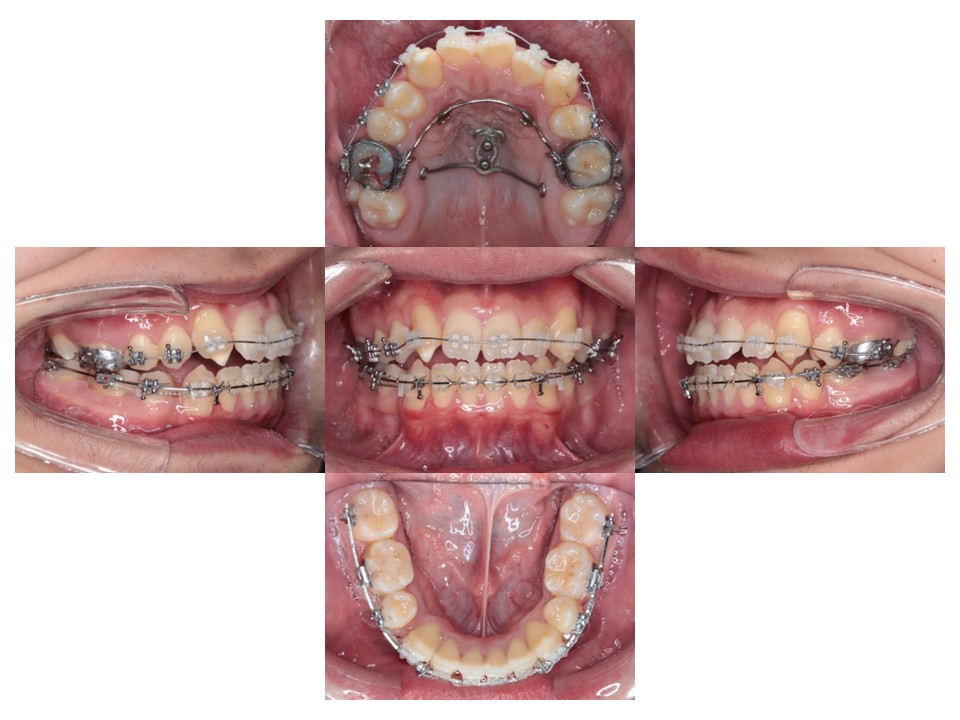

上あごにネジを打って全体的に歯を並べています